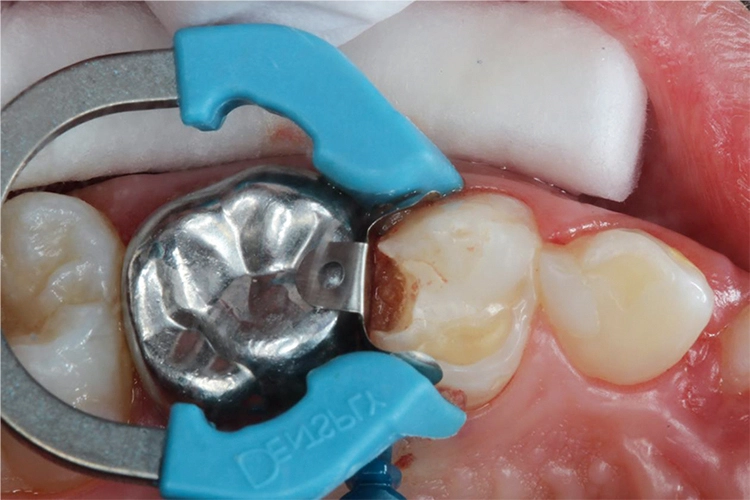

Bei einem Kontrolltermin eines 8-jährigen Jungen imponierte eine insuffiziente Füllung im linken Oberkiefer (Abb. 1). Die Anfertigung eines halbseitigen Orthopantomogramms (OPG) zeigte eine koronale Aufhellung an Zahn 64 distal (Abb. 2). Aufgrund der vollständigen mesialen Wurzel entschied man sich für den Erhalt des Zahnes 64 und eine Restauration mit einem plastischen Füllungsmaterial.

Möhn, KrämerHierfür wurde die Kavität zunächst mit einem birnenförmigen Diamanten aufgezogen und das kariöse Dentin mit einem Polymerbohrer schonend exkaviert (Abb. 3). Für die Formgebung und den Schutz des Nachbarzahnes wurde das Teilmatrizensystem Palodent® V3 verwendet (Abb. 4). Im Anschluss folgte die Füllungstherapie mittels Surefil one™ in Farbe A2.